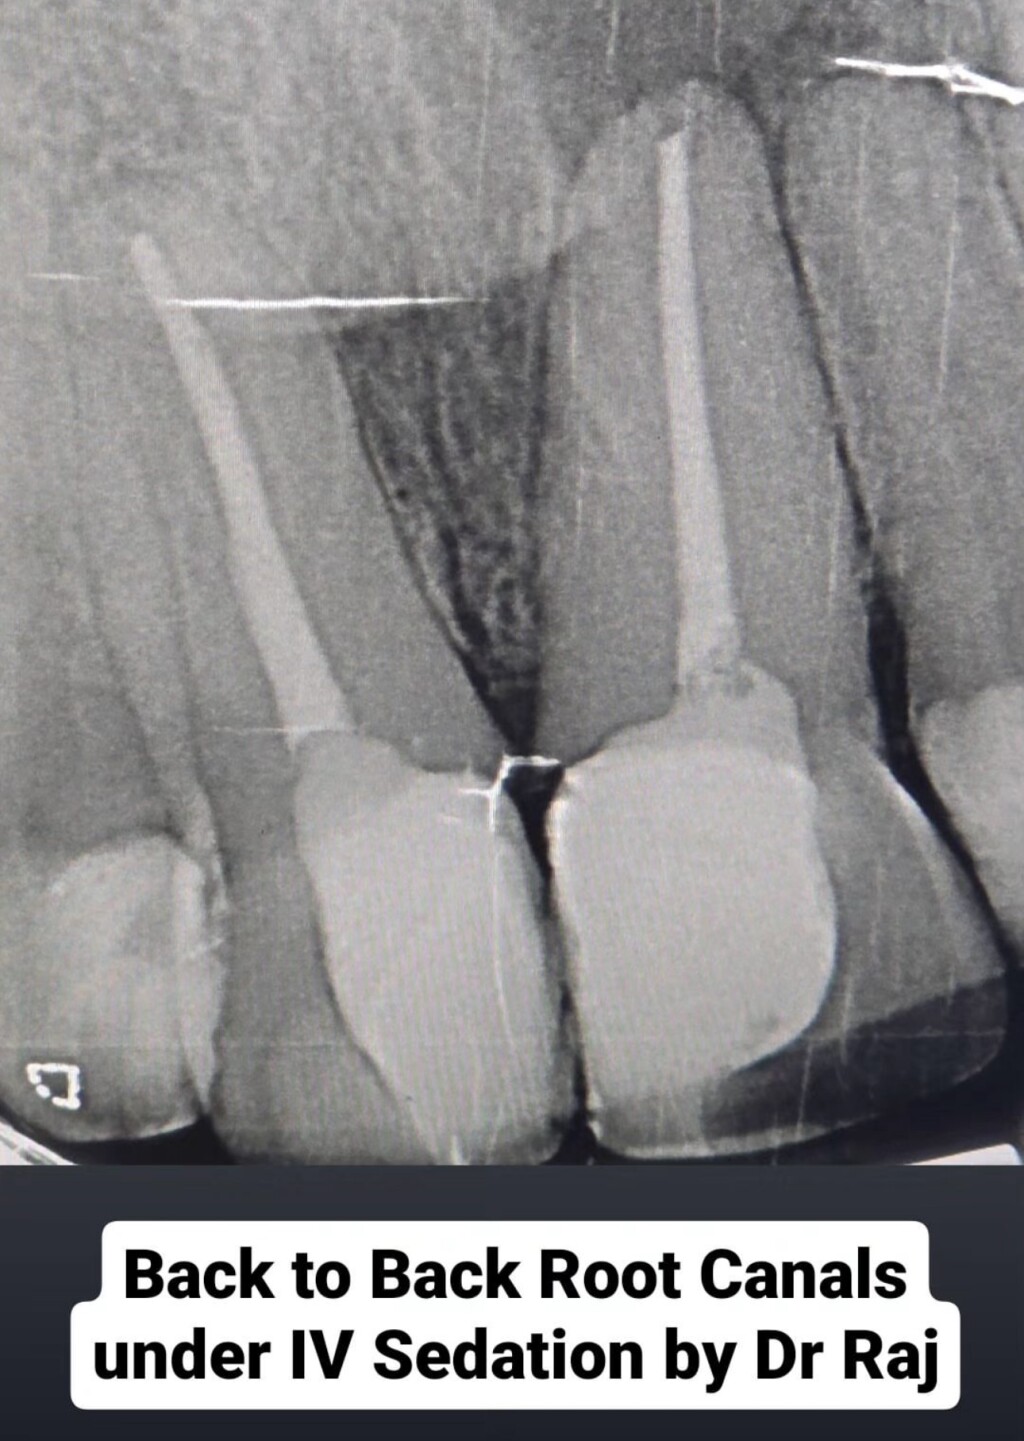

Totally painless dental care under IV Sedation so our pateints wont remember or feel a thing!

Today we completed extractions, fillings, gum treatment and even a root canal under sedation!